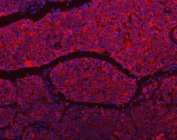

Immunofluorescent staining of FFPE human liver cancer tissue with SLU7 antibody (red) and DAPI nuclear stain (blue). HIER: steam section in pH6 citrate buffer for 20 min.